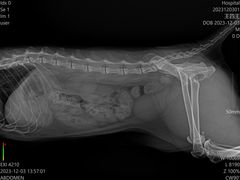

• -艾贝尔宠物诊疗

nyannyan | 23-12-04

报错